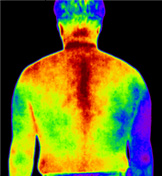

적외선 체열검사 DITI (Digital Infrared Thermal Imaging)

- X-ray, MRI 등으로 확인할 수 없는 신경통, 근육통 등을 확인하기 위하여 적외선을 이용하여 체열 분포의 변화를 확인하는 검사

- 통증이 있는 부위에서는 교감, 부교감 신경의 작용으로 체열이 높거나 낮게 측정되므로 이러한 변화를 측정하여 정확한 통증 부위를 확인 가능

질병에 따른 DITI 분석

오십견